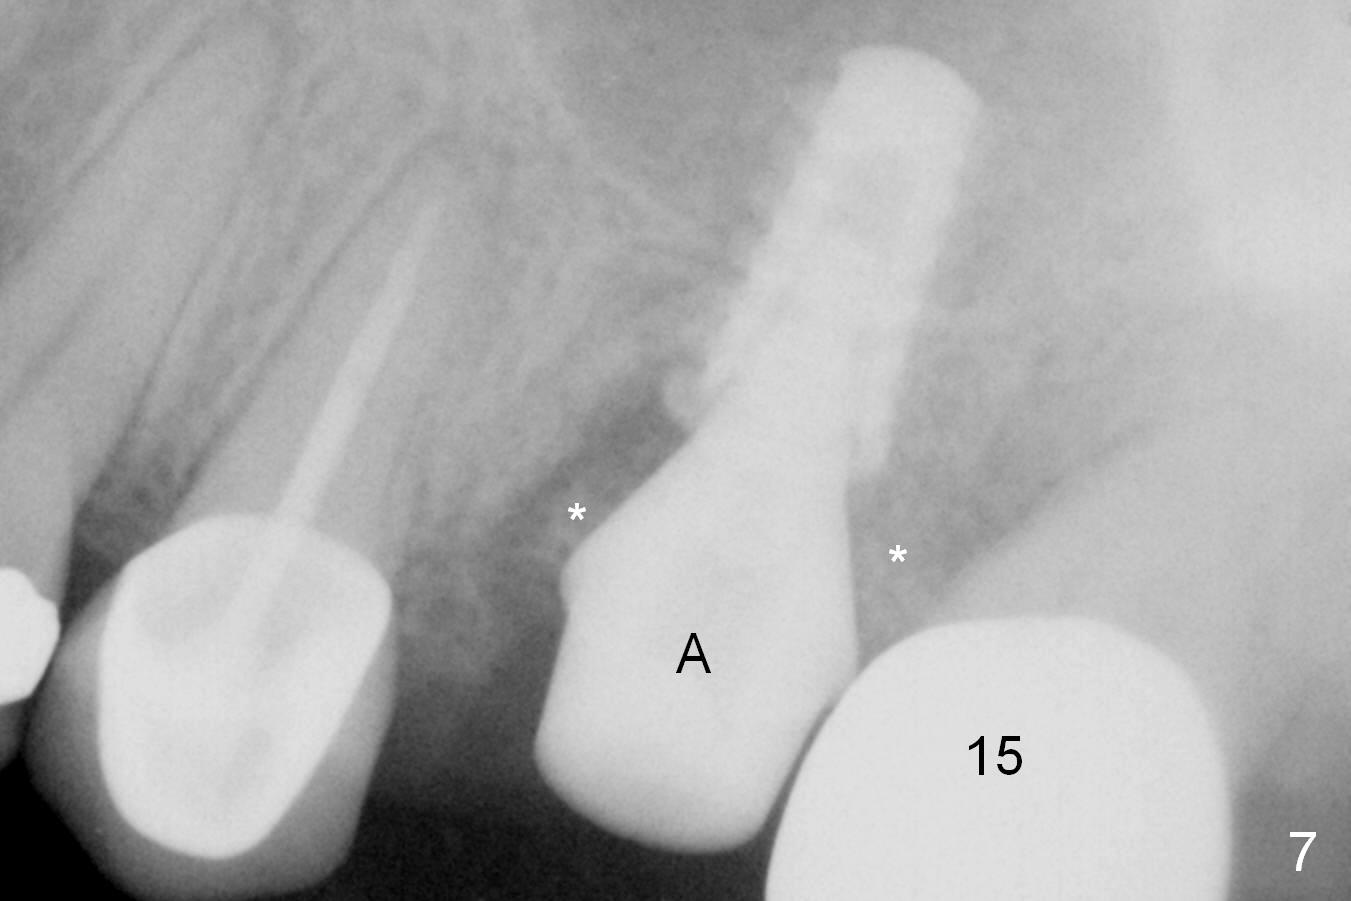

When the affected tooth is extracted, the suitable site for implantation is the large palatal socket. Osteotomy is initiated with Magic Expander 3.0 mm (red circle or arrow in Fig.1 (occlusal view), 2 ((coronal section)) as buccally as possible, since the palatal plate (P) is shorter than the buccal one (B in Fig.2). The sinus floor turns out to be thin. When the osteotomy at the sinus floor increases equivalent to the apical diameter of a 5 mm implant, a 5x9 mm dummy one is placed (Fig.6). There are two errors, one recognized immediately, the other not. The implant is placed too apically, but the sinus membrane remains intact. After placing 2 pieces of PRF membrane and allograft (.5-1.0 mm), a larger implant is placed (5.5x9 mm IBS) is placed at the palatal crestal level (Fig.4) with minimal stability. When a 6.5x4(4) mm abutment is being placed, it turns the underlying implant so that the latter is placed more apically (Fig.5,7). Ideally, a much larger implant should have been chosen (6.0 or 6.5 mm, Fig.3 green circle). In the future, tap drills should be used prior to implantation if the sinus floor is thin. The abutment in this case (Fig.7 A) is close to the tooth #15. The latter is the 2nd error not recognized earlier (Fig.6). The trajectory should have been corrected when a more definitive implant is being placed (from black line to red line).

The patient is doing well 9 days postop. The immediate provisional is loose and over-sized. It is removed for trimming and reline; the socket and bone graft (Fig.8 *) are healing. It appears that an angled abutment is required next time of provisional revision. When an angled abutment is being placed 23 days postop (Fig.9), it appears to wiggle the implant due to its long leverage. Instead a healing abutment is placed. The implant is unstable 4.5 months postop with seemingly excessive bone-implant gap (Fig.10 <). The 5.5x9 mm implant is removed. A 5x17 mm tap is used to change the trajectory and sinus lift, followed by 6x17 one (Fig.11). Finally a 6x14 mm tissue-level implant is placed with insertion torque > 50 Ncm (Fig.12; vs. <20 Ncm (Fig.7,10)) and improved trajectory. An immediate provisional is fabricated to prevent the mesial drifting of the tooth #15 (Fig.13 P (*: occlusal clearance)). By using the taps and placing the longer implant, the sinus lift is more obvious (compare Fig.10 and 12 (*)). Sinus lift remains evident 3.5 months postop (Fig.14) with apparently osteointegration (Fig.15).